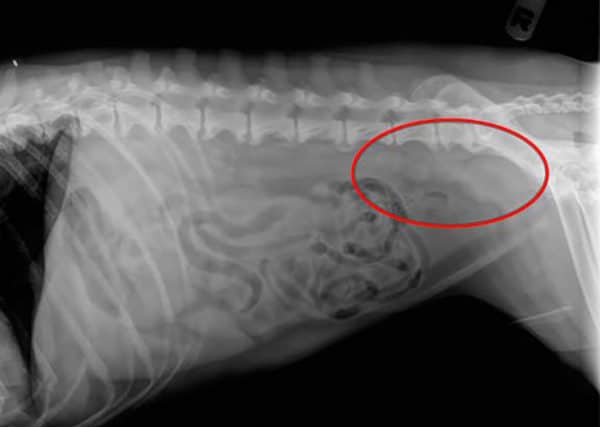

X-ray showing stomach distention in a GDV bloat

This is the radiograph of the stomach of a dog with bloat. It is twisted on itself, so it also has volvulus.

If you dog is lethargic, is drooling thick saliva, or appears bloated, it could have GDV (gastric dilatation and volvulus). This is an emergency, and should be checked immediately if you poodle shows any of these symptoms.